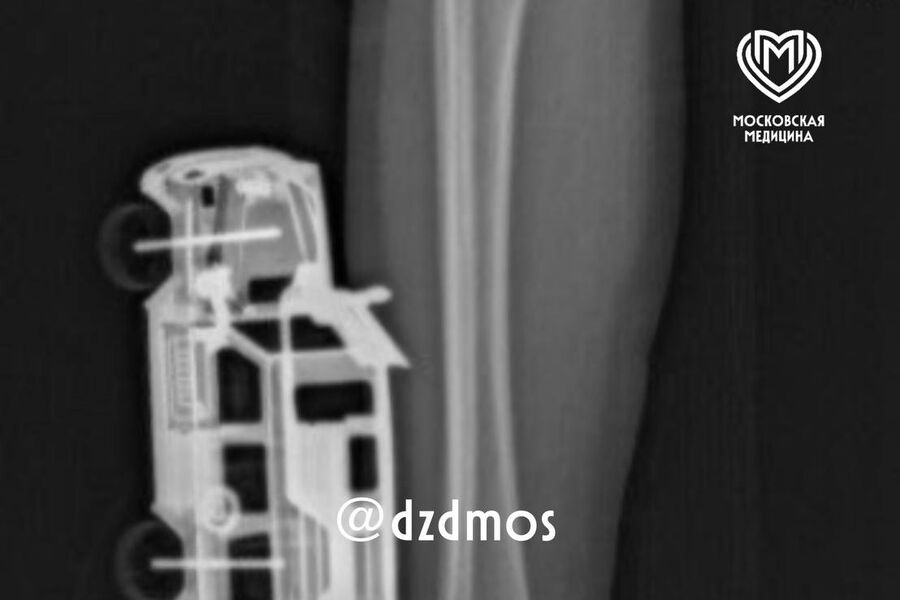

По словам родителей, ребенок прыгнул с кровати у себя дома и неудачно упал на игрушку правой голенью. Машинка повредила мягкие ткани, ее части вошли глубоко и достигли подкожножировой клетчатки.

Пострадавшего мальчика доставили в больницу, где ему сделали рентген, чтобы исключить повреждение костей. После этого медики удалили игрушку и провели хирургическую обработку образовавшейся на ноге ребенка раны. Через сутки малолетнего пациента уже выписали домой.